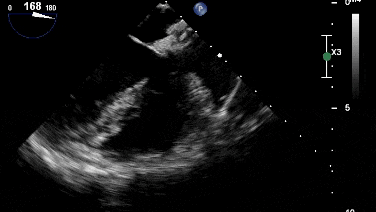

封堵器釋放后成型良好,無殘余分流

沿加硬導絲將9F輸送鞘送至左心房,退出導絲及輸送鞘內芯后,在超聲引導下送入1824PFO封堵器進行封堵。先釋放左盤面,整體回撤,緊貼房間隔,后釋放右盤面,進行推拉試驗,超聲在主動脈短軸切面、四腔心切面確認封堵器對二尖瓣等周圍組織無影響,位置及形態良好后釋放封堵器。撤出長鞘、縫合穿刺點后壓迫止血,加壓繃帶包扎,手術結束。